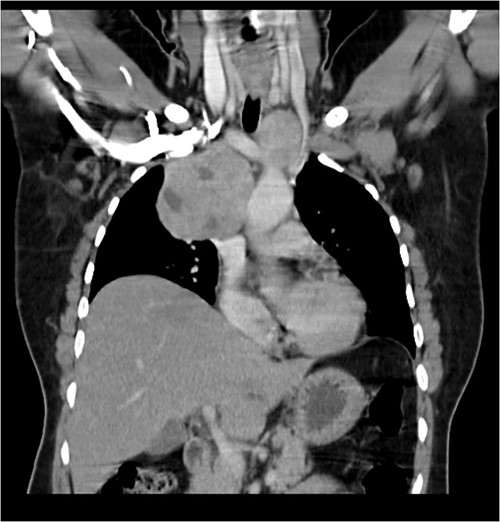

A 57-year-old female came with chest discomfort and cough since 1 month. The chest X-ray (Fig. 1) showed mass in the superior mediastinum. CECT thorax (Fig. 2) revealed the soft tissue density 7 cm × 7 cm (Fig. 3) in superior mediastinum abutting subclavian artery, azygous vein, anteriorly displacing superior venacava, anteromedially abutting arch of aorta, posteromedially compressing trachea and abutting right main bronchus. A 4.9 cm × 5 cm mass in the left side superior mediatinum was seen abutting internal jugular vein and brachiocephalic artery. USG showed the presence of normal thyroid in the neck. CT guided biopsy from the right mass showed ectopic thyroid tissue (ETT)-colloid goiter. Due to close proximity with major vessels sternotomy done. Mass in the left side 5 cm × 5 cm (Fig. 4) in the superior mediastinum was identified, on dissecting superiorly, which was free from the thyroid in the neck and abutting the IJV, brachiocephalic artery and left innominate vein that were separated with meticulous dissection.

The right mass (Fig. 5) was even bigger and needed an extension of incision into the neck (Fig. 6). About 7 cm × 7 cm noted to be displacing Superior venacava anteriorly that was dissected from it, separated from the first rib and subclavian artery meticulously taking care not to damage any major structure. Both masses were excised. These masses were not connected in any way with each other as well as with the orthotopic thyroid in the neck. Post-op was uneventful. Thyroid functions were normal. Thyroid scan (Fig. 8) showed no evidence of a thyroid tissue in the mediastinum and no other ectopic thyroid was present other than the orthotopic thyroid tissue in neck. The patient was discharged on POD 10 without any symptoms. The histopathological tissue diagnosis showed a colloid goiter (Fig. 7). All data kept in our database.